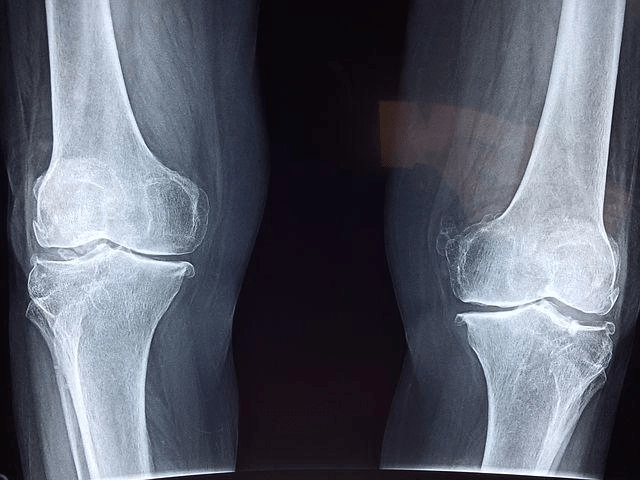

우리 몸속 관절 사이에는 연골이라는 조직이 존재하는데 외부로부터 오는 충격을 흡수하며 뼈끼리 마찰되지 않도록 도와주는 역할을 합니다.

하지만 세월이 흐르면 자연스럽게 퇴행성 변화가 일어나게 되는데 이로 인해 통증 및 염증이 발생하기도 합니다. 따라서 이를 예방하기 위해서는 평소 꾸준한 관리가 필요한데요. 이때 도움 되는 성분이 바로 콘드로이친입니다.

연골 내에서 수분 다음으로 많은 비중을 차지하고 있는 주성분이 바로 콘드로이친입니다. 연골 구조의 뼈대, 지지대,연골의 탄성력에 중요한 역할을 하고 있습니다.

그러나 나이가 들수록 콘드로이친이 감소되고 연골이 짧아지고, 끊어지기도 합니다.

관절 통증과 관절염의 원인은 바로 연골 손상입니다. 콘드로이친 황산은 나이가 들수록 감소하기 때문에 외부로부터 섭취가 필요합니다. 그래서 반드시 건강기능식품으로 섭취해야 합니다.